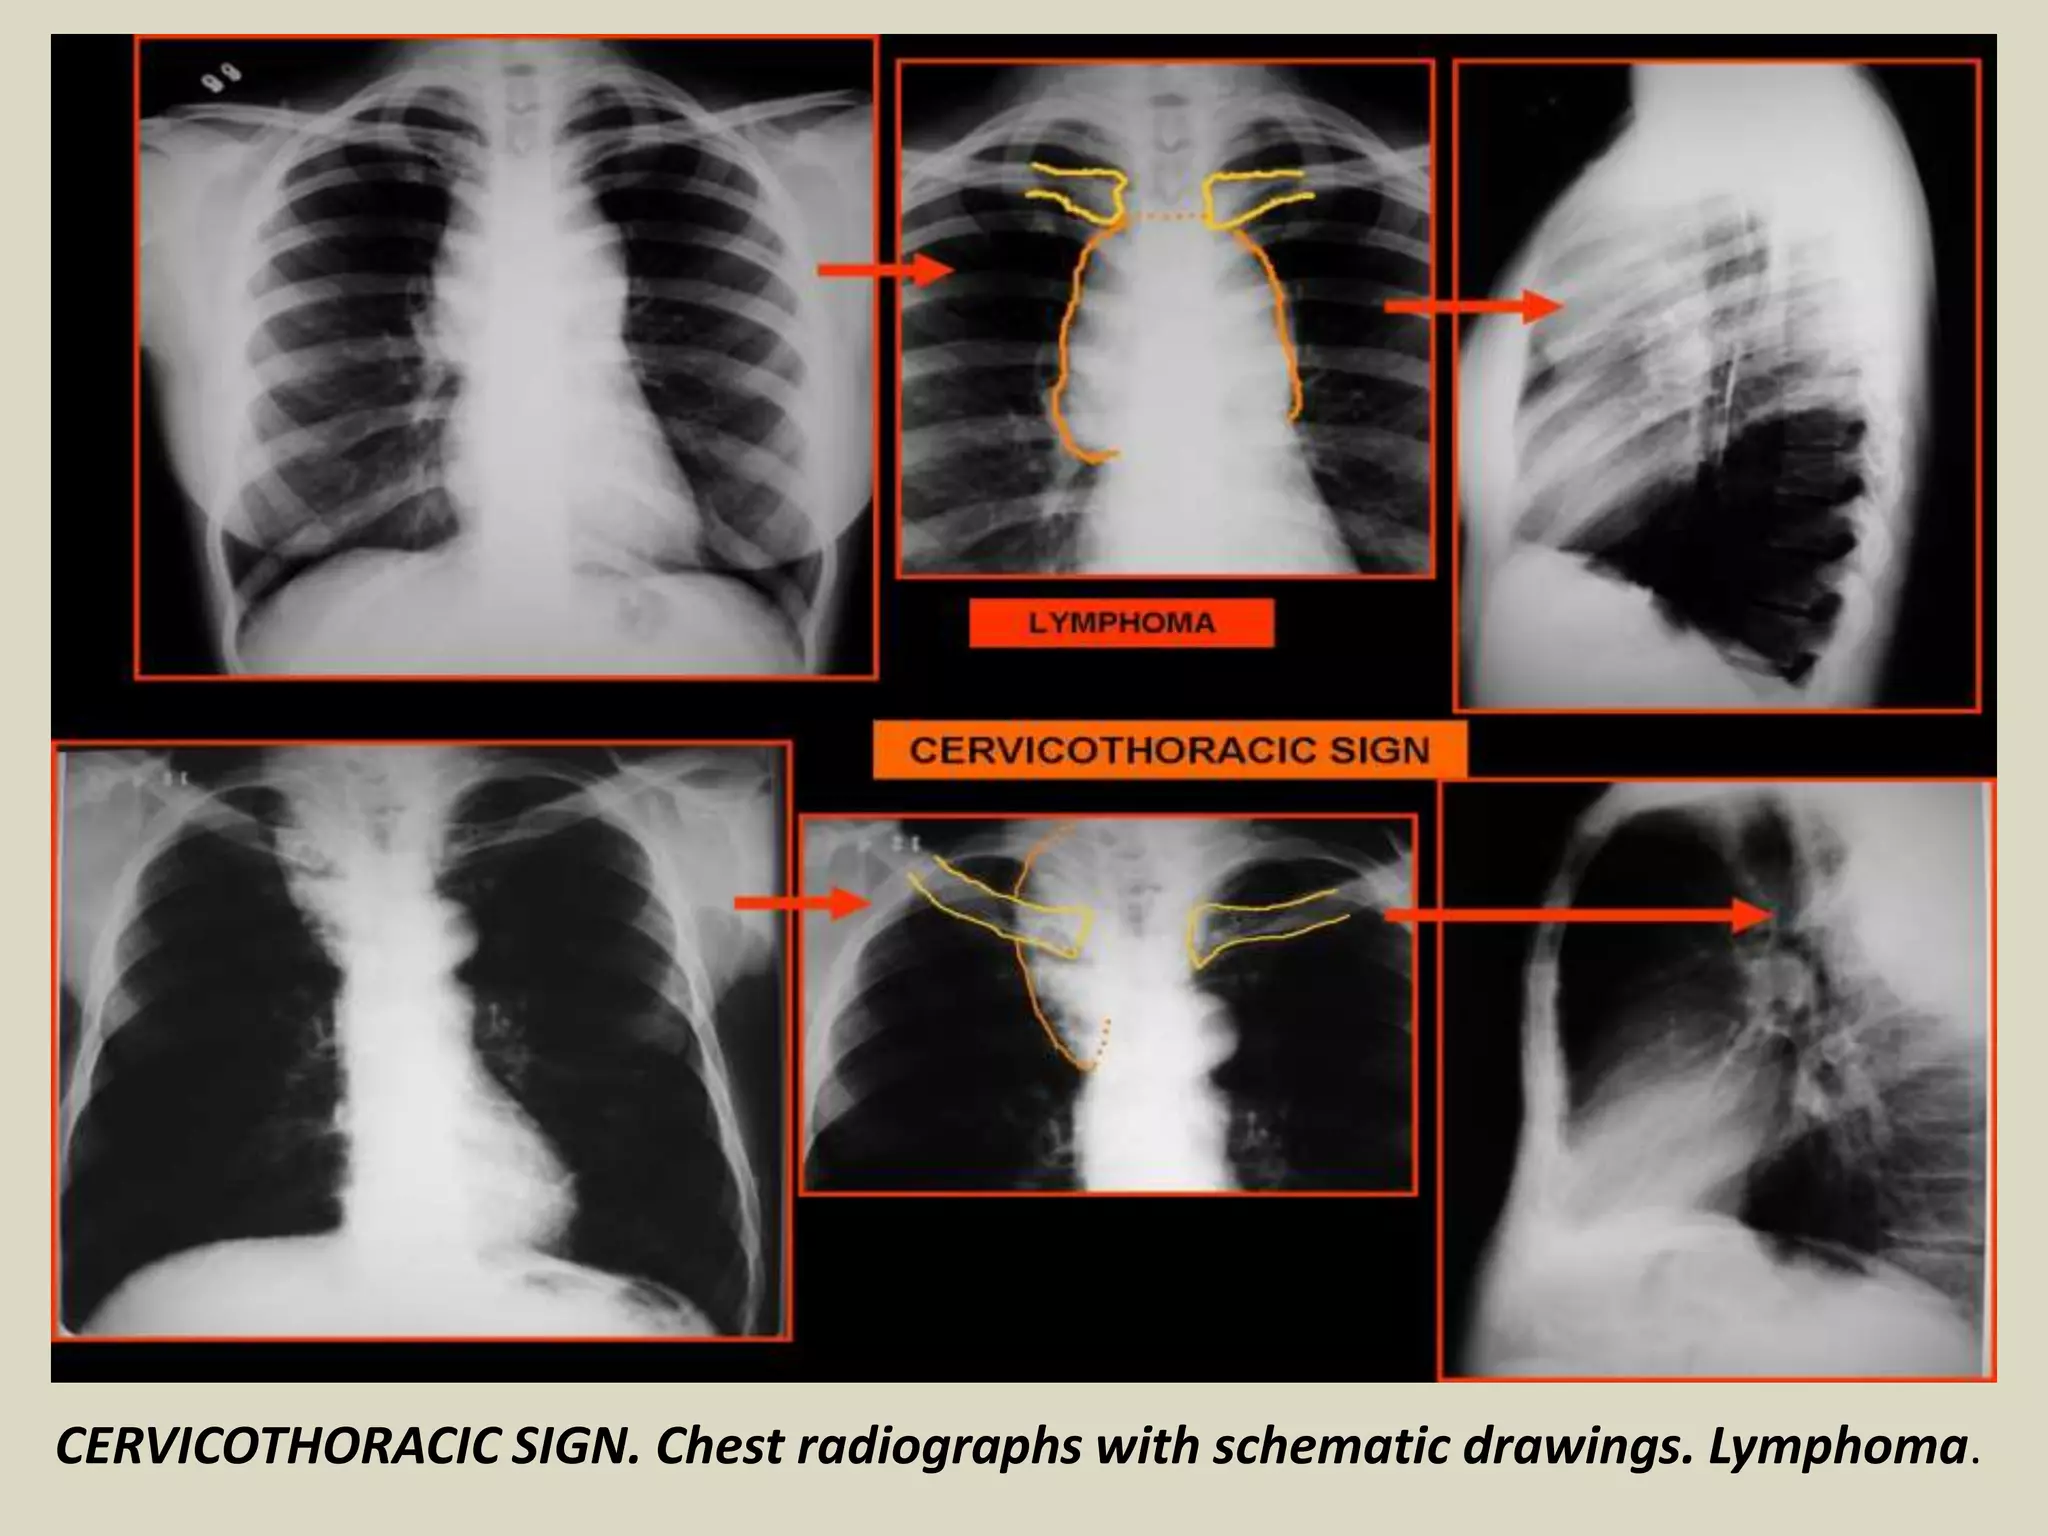

CERVICOTHORACIC SIGN

Used to determine location of mediastinal lesion in the upper

chest

Based on principle that an intrathoracic lesion in direct contact

with soft tissues of the neck will not be outlined by air

Uppermost border of the anterior mediastinum ends at level

of clavicles, so when the cephalic border of a mass is obscured

at or below the level of the clavicles, it is deemed to be a

“cervicothoracic lesion” involving the anterior mediastinum

Middle and posterior mediastinum extends above the clavicles

Mediastinal mass projected superior the level of clavicles must

be located either within middle or posterior mediastinum

More cephalad the mass extends the most posterior the

location

CERVICOTHORACIC SIGN. Chest radiographs with schematic drawings. Lymphoma.

CERVICOTHORACIC SIGN Used todetermine location of mediastinal lesion in the upper chest Based on principle that an intrathoracic lesion in direct contact with soft tissues of the neck will not be outlined by air Uppermost border of the anterior mediastinum ends at level of clavicles, so when the cephalic border of a mass is obscured at or below the level of the clavicles, it is deemed to be a “cervicothoracic lesion” involving the anterior mediastinum Middle and posterior mediastinum extends above the clavicles Mediastinal mass projected superior the level of clavicles must be located either within middle or posterior mediastinum More cephalad the mass extends the most posterior the location

CERVICOTHORACIC SIGN. Chestradiographs with schematic drawings. Lymphoma.